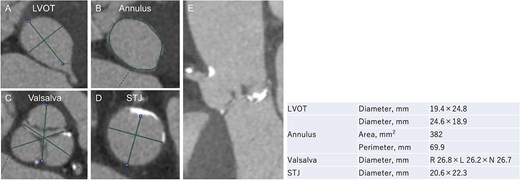

An 88-year-old woman with severe symptomatic AS (aortic valve area: 0.40 cm2; peak velocity: 4.9 m/s; mean pressure gradient: 56 mm Hg) and ischemic heart disease with severe stenosis in the proximal segments of both the left anterior descending (LAD) coronary artery and circumflex arteries was referred from another hospital for invasive treatment. The patient was taking edoxaban 30 mg, nifedipine 20 mg, perindopril 4 mg, and candesartan 8 mg for the treatment of atrial fibrillation and hypertension. The patient’s perioperative risk was high, with a Society of Thoracic Surgeon (STS) score of 9.31% and Logistic EuroSCORE of 23.11%. Following discussion with the heart team, we decided to perform TAVI before coronary revascularization, with percutaneous coronary intervention (PCI) planned postoperatively. We evaluated the aortic valve complex using contrast-enhanced computed tomography (CT), which revealed a narrow sinotubular junction (STJ) with small calcifications measuring 20.6 × 22.3 mm (Fig. 1). TAVI was performed via a transfemoral approach under local anesthesia and sedation. A 23-mm SAPIEN 3 THV (Edwards Lifesciences, Irvine, CA, USA), which provides better coronary access due to its shorter frame length and relatively larger cell size, was deployed without prior balloon aortic valvuloplasty. To minimize the risk of injury to the STJ, the THV was deployed with a reduced balloon volume (−1 cc), and post-dilatation was conducted with the balloon positioned toward the left ventricular side (Fig. 2). Postoperatively, the patient’s blood pressure stabilized with rest and a reduced-sodium diet, allowing modification of the antihypertensive therapy to sacubitril/valsartan 100 mg alone. Additionally, aspirin 100 mg was added to ongoing edoxaban therapy for the planned PCI. The postoperative course was uneventful, and the patient was subsequently discharged. However, on day 4 after discharge, the patient experienced acute chest discomfort. Blood tests, electrocardiography, and transthoracic echocardiography revealed no significant changes from the time of discharge, and the patient was sent home as the symptoms gradually improved. On day 7 after discharge, contrast-enhanced CT—originally scheduled as a preoperative assessment for PCI at the referring hospital— incidentally revealed a localized dissection of the ascending aorta. The entry point of the dissection was located at the STJ extending toward the THV stent frame, consistent with Stanford AAD associated with TAVI (Fig. 3). The patient was transferred to our hospital and underwent surgery, including aortic valve replacement, ascending aorta replacement, and coronary artery bypass grafting (left internal thoracic artery to the LAD and saphenous vein graft to the obtuse marginal branch). Intraoperatively, removal of the THV and calcified STJ tissue revealed a pinhole-like intimal defect, which was continuous with a hematoma within the media and identified as the entry point of the dissection. Macroscopic pathological examination of the resected ascending aorta also confirmed the presence of a small intimal defect (Fig. 4). This intimal injury was therefore considered to have resulted from compression of the calcified tissue caused by THV implantation. After ~1 month of rehabilitation, the patient was discharged in an ambulatory state on postoperative day 30.

Evaluation of the aortic valve complex using contrast-enhanced CT shows axial views (A–D) and a curved multi-planar reconstruction (E) with a narrowed sinotubular junction and small calcifications (LVOT: left ventricular outflow tract; STJ: sinotubular junction).